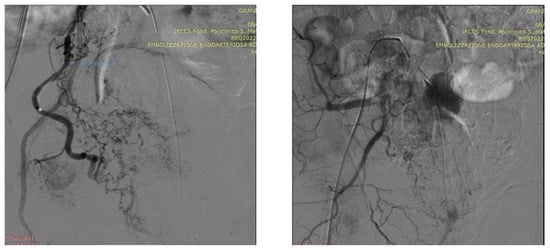

Technical Details of PAE